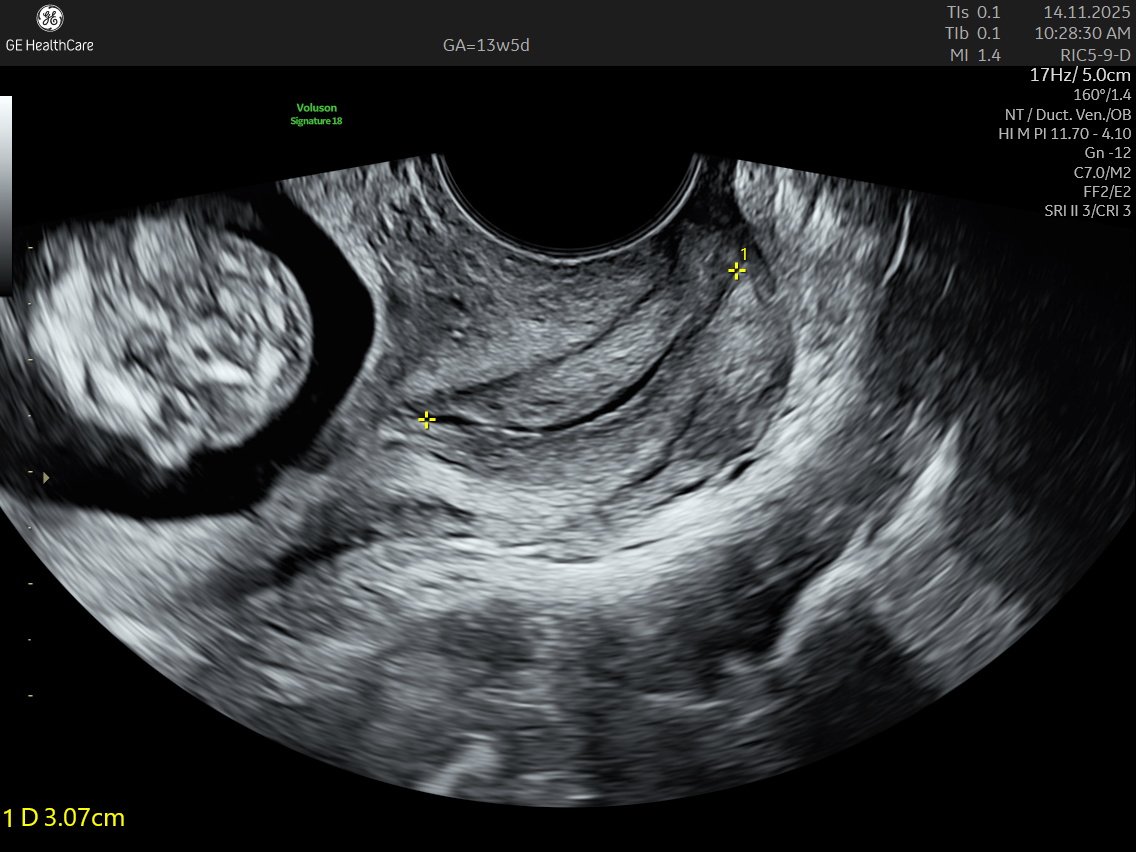

The NT scan is a non-invasive ultrasound examination conducted in the first trimester (12–13 weeks). It measures the nuchal translucency (the fluid at the back of the fetus’s neck) and combines it with the maternal blood test for a detailed risk profile. NT Scan is an important early screening test for Down syndrome (Trisomy 21), Edwards syndrome (Trisomy 18), and Patau syndrome (Trisomy 13).

The NT scan measures the fluid-filled space at the back of the fetal neck, and an increased NT measurement (typically 3.5 mm or more) may indicate a higher risk for:

Although the NT scan is mainly a screening tool and not diagnostic on its own, it can identify about 50% of major fetal abnormalities when combined with other assessments like blood tests and detailed ultrasound. The scan also helps to screen some basic anatomical structures during the first trimester, especially the fetal heart anatomy, brain, face, spine, stomach, abdominal wall, kidneys, bladder, and extremities to varying degrees depending on gestational age and maternal factors.